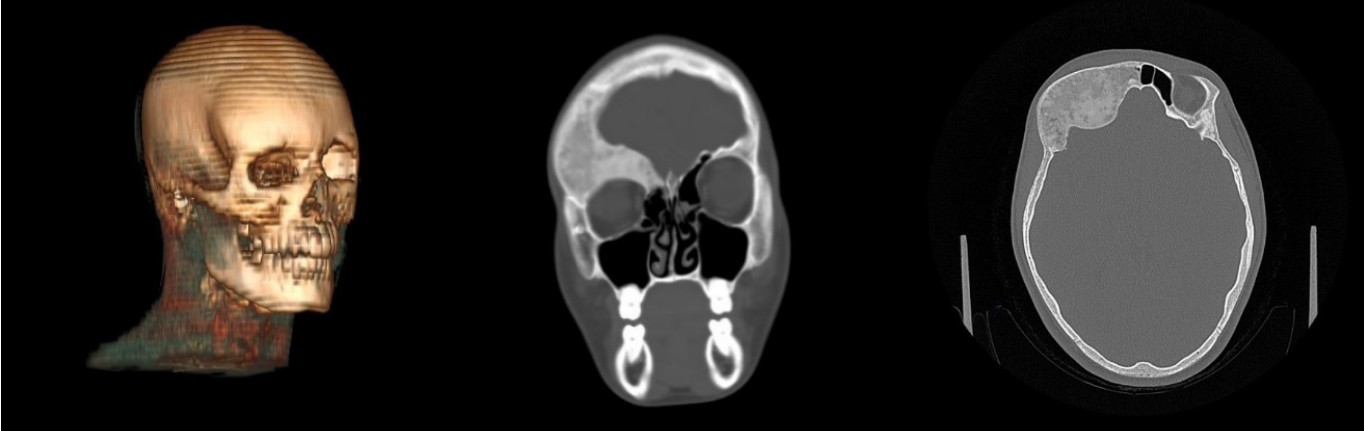

A 7‑years-old girl presented with painless swelling over the left side of her frontal bone region since 2019, CT scan of the skull was performed, and she was primary diagnostic with polyostotic form of fibrous dysplasia. The patient had no history of trauma, or other associated disease related to FD. Consulted in the outpatient department of the RCCH for the first time in 2022, where hospitalization was recommended and the patient was admitted to the maxillofacial surgery department.

Diagnosis

The MSCT imaging revealed affected osseous structure diffuse ill-defined expansible ground glass lesion appearance involving craniofacial region. Notably there was a periosteal thickening along the anterior surface of the left frontal and partial bone. Clinically, a change in the configuration of the face was visualized without pain (Figures 1, 2).

Fig. 1. MSCT (3D cut) showing bony expansion over the left frontal bone region in preoperative stage on 2022

Fig. 2. Preoperative axial computed tomographic image exhibiting characteristic ground-glass opacification of fibrous dysplasia involving the left frontal